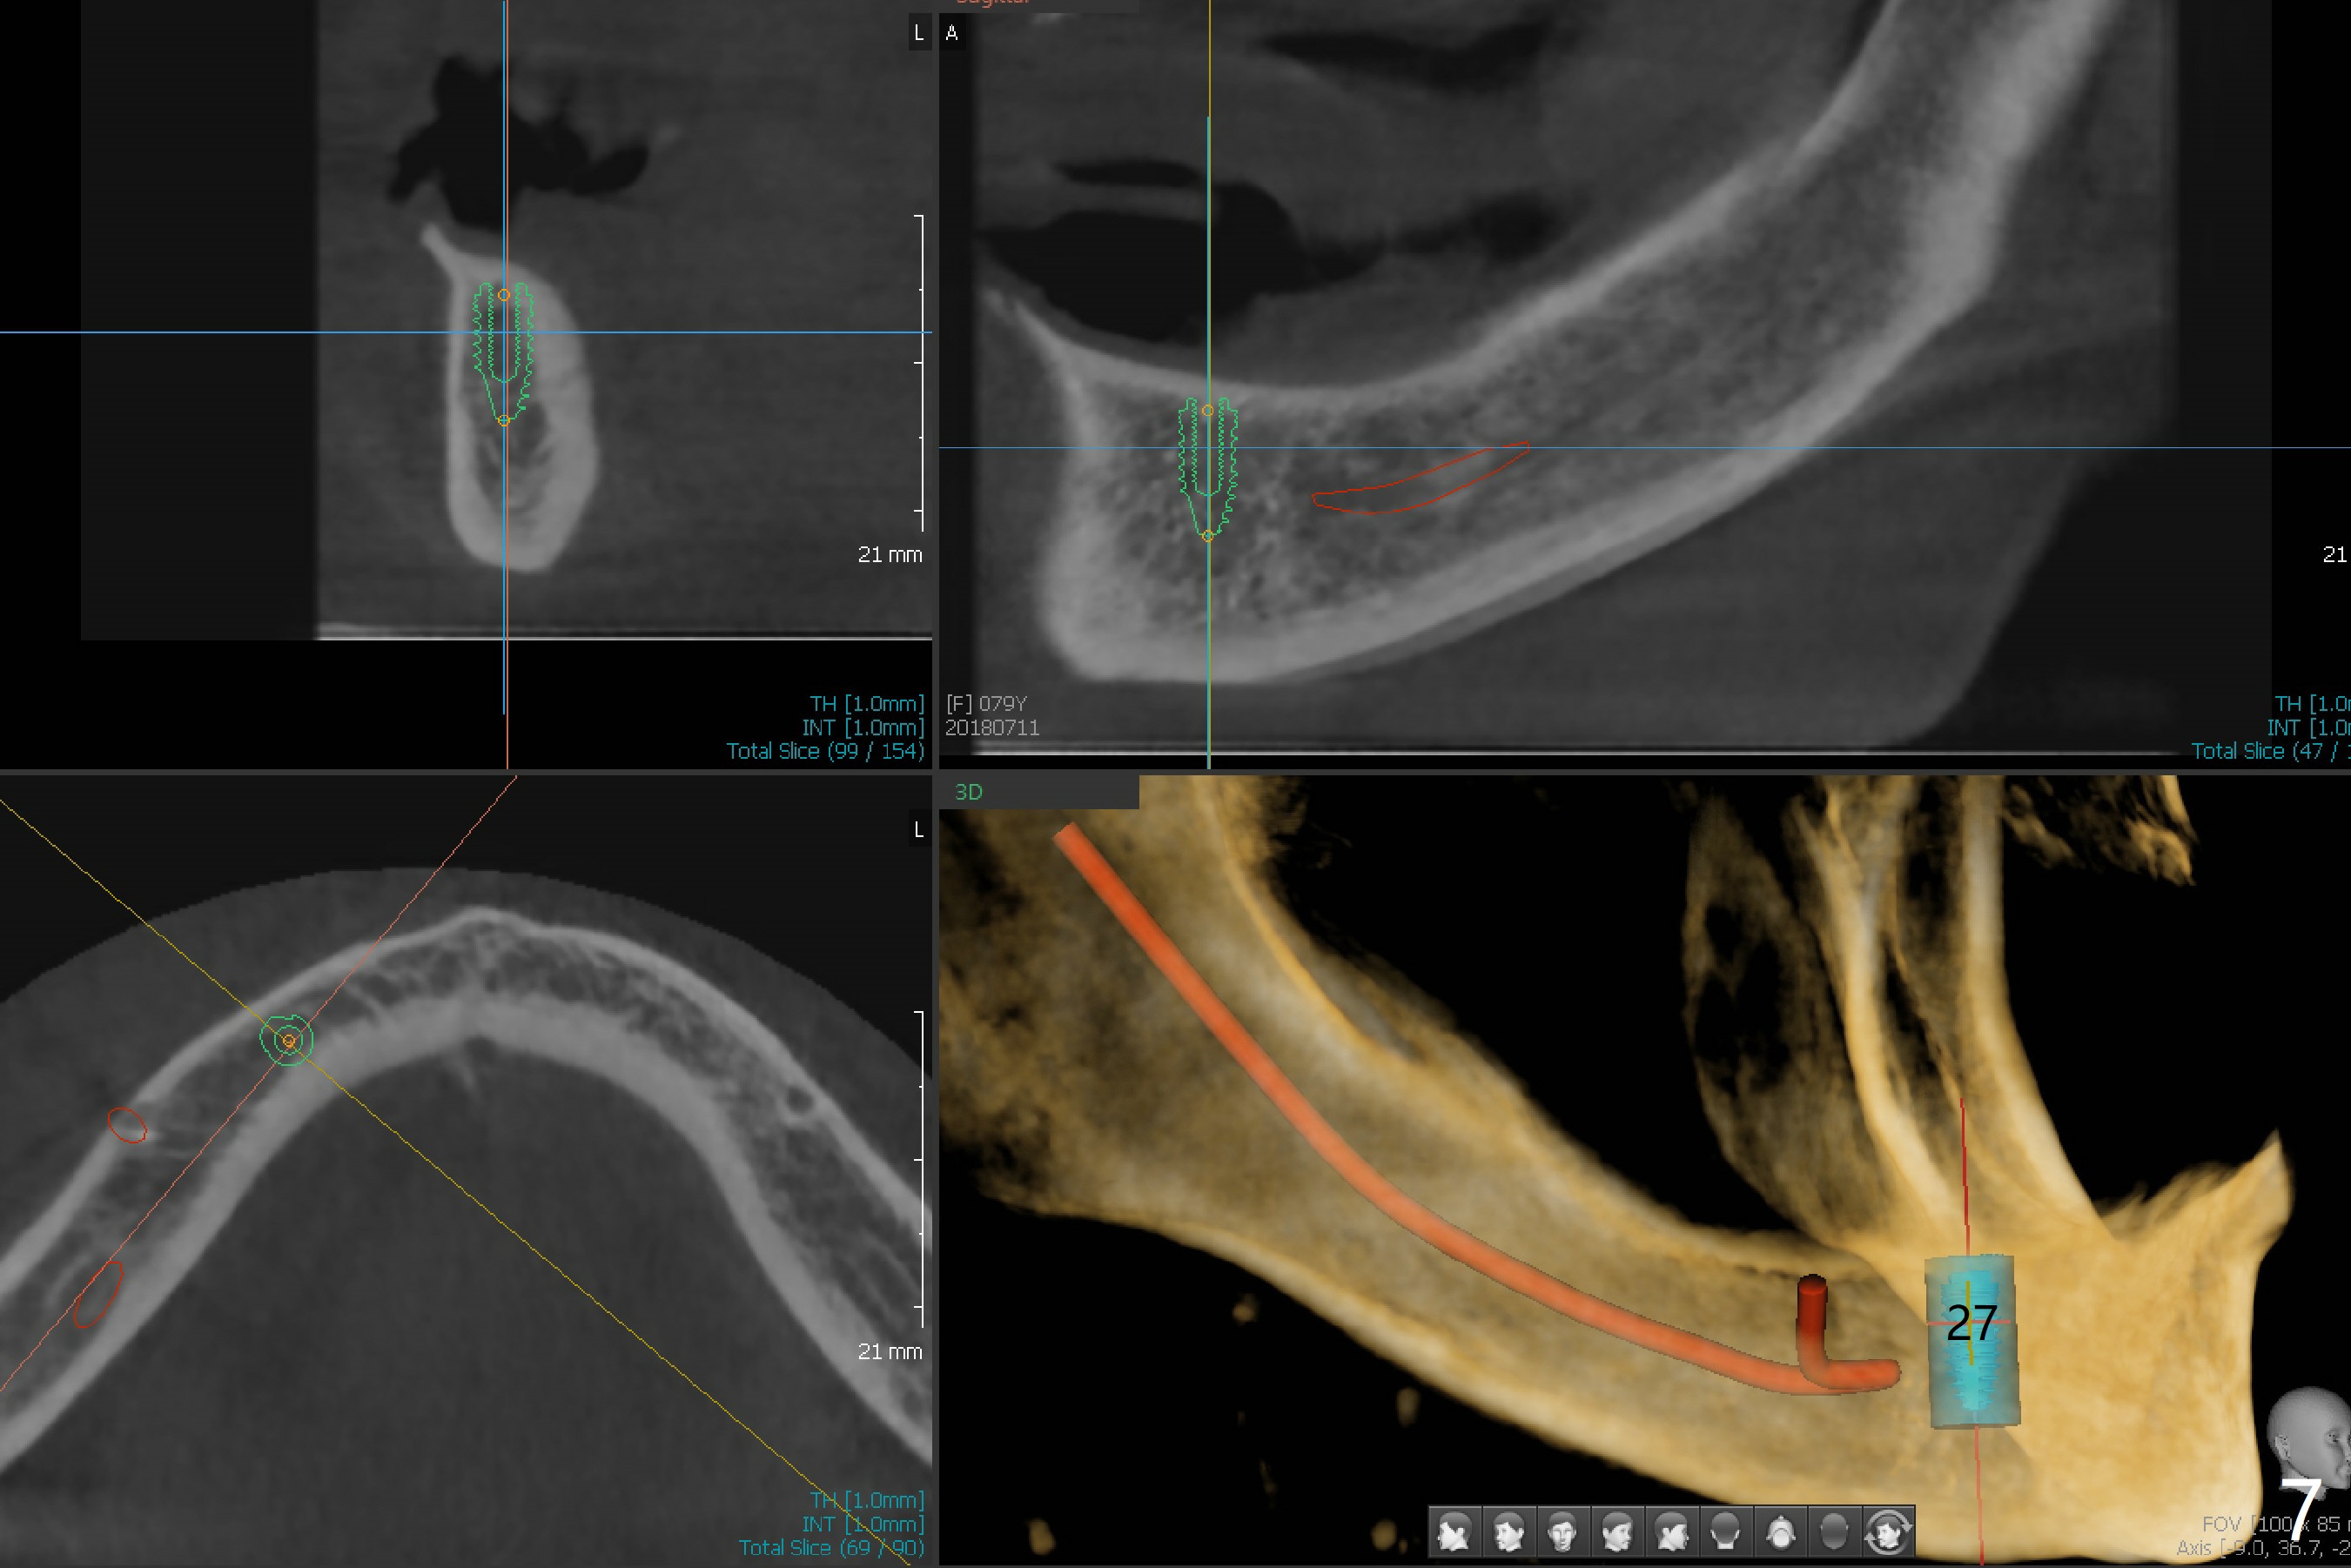

A 79-year-old woman is not pleased with cross bite and no tooth exposure of the upper complete denture (Fig.1-4). Her immediate concern is the loose lower RPD (Fig.5) after loss of the tooth #21 (Fig.6). The tooth #22 has mobility II. SM narrow implants will be placed at #22 and 27 immediately after #27 extraction (Fig.7,8). Ball abutments are going to be inserted prior to soft reline of the lower RPD. Prepare an acrylic bur to make a receptacle in the RPD for #27 abutment and high speed handpiece to section the tooth #22 as a denture tooth (prepare hard pink acrylic)